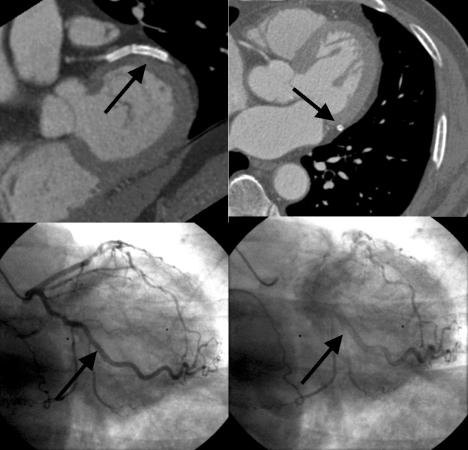

Contrast-enhanced multi-detector row spiral computed tomography (MDCT) was introduced as a promising noninvasive method for vascular imaging. This study examined the accuracy of this technique for detecting significant coronary artery stenoses. Both MDCT(Sensation 16, Siemens, Germany, 12x0.75 mm collimation and 0.42 sec rotation speed, 120 kV, 500 effective mA, and 2.7 mm/rotation table-feed) and invasive coronary angiography (CAG) were performed on 61 patients (mean age 59.2+/-10, 44 men) who were suspected of having coronary artery disease. All patients were treated with atenolol (25-50 mg) prior to imaging and the heart rate was maintained below 65 beats per minutes during image acquisition. The images were reconstructed in the diastole around TI-400 ms with a 0.5 mm increment and a 1.0 mm thickness. All coronary arteries with a diameter of 2.0 mm or more were assessed for the presence of a stenosis (>50% luminal narrowing). Two independent radiologists who were unaware of the results of the invasive CAG evaluated the MDCT data, and the results were compared with those from the invasive CAG (interval 1-27, mean 11 days). An evaluation of the CT coronary angiogram (CTCA) was possible in 58 of the 61 patients (95%). Image acquisition of the major coronary arteries including the left main trunk was available in 229 out of 244 arteries. Invasive CAG showed that 35 out of 58 patients had significant coronary artery stenoses by. patient analysis of those who could be evaluated showed that CT coronary angiography correctly classified 30 out of 35 patients as having at least 1 coronary stenosis (sensitivity 85.7%, specificity 91.3%, positive predictive value 93.8%, negative predictive value 80.8%). By analyzing each coronary artery, CAG found 62 stenotic coronary arteries in the 229 coronary arteries that could be evaluated. MDCT correctly detected 50 out of 62 stenotic coronary arteries and an absence of stenosis was correctly identified in 156 out of 167 normal coronary arteries (sensitivity 80.6%, specificity 93.4%, positive predictive value 81.9%, negative predictive value 92.8%). The non-invasive technique of MDCT for examining the coronary artery appears to be a useful method for detecting coronary artery stenoses with a high accuracy particularly with the proximal portion and large arteries.

对比增强型多排螺旋计算机断层扫描(MDCT)作为一种有前景的血管成像无创方法被引入。本研究检测了该技术检测显著冠状动脉狭窄的准确性。对61例疑似患有冠状动脉疾病的患者(平均年龄59.2±10岁,44例男性)同时进行了MDCT(德国西门子Sensation 16,准直12×0.75mm,转速0.42秒,120kV,有效毫安500,床进速度2.7mm/旋转)和有创冠状动脉造影(CAG)检查。所有患者在成像前均接受阿替洛尔(25 - 50mg)治疗,且在图像采集期间心率维持在每分钟65次以下。图像在舒张期TI - 400ms左右重建,增量为0.5mm,层厚为1.0mm。对所有直径2.0mm及以上的冠状动脉评估是否存在狭窄(管腔狭窄>50%)。两名不知有创CAG结果的独立放射科医生评估MDCT数据,并将结果与有创CAG的结果进行比较(间隔1 - 27天,平均11天)。61例患者中有58例(95%)可行CT冠状动脉造影(CTCA)评估。244支动脉中有229支获得了包括左主干在内的主要冠状动脉的图像采集。有创CAG显示,58例患者中有35例存在显著冠状动脉狭窄。对可评估患者的分析显示,CT冠状动脉造影将35例患者中的30例正确分类为至少有1处冠状动脉狭窄(敏感性85.7%,特异性91.3%,阳性预测值93.8%,阴性预测值80.8%)。通过分析每支冠状动脉,CAG在229支可评估的冠状动脉中发现62支狭窄冠状动脉。MDCT正确检测出62支狭窄冠状动脉中的50支,在167支正常冠状动脉中的156支正确识别出无狭窄(敏感性80.6%,特异性93.4%,阳性预测值81.9%,阴性预测值92.8%)。MDCT这种用于检查冠状动脉的无创技术似乎是一种检测冠状动脉狭窄的有用方法,尤其对于近端部分和大动脉具有较高的准确性。